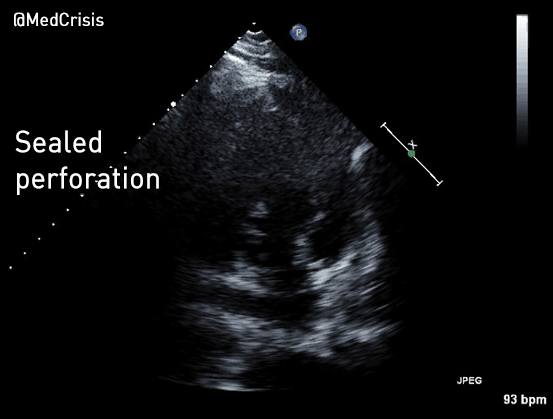

Apical 2 chamber. This view demonstrates the bulging from the RV also appears to involve the LV. This is a sealed perforation with aneurysm formation.

In this remarkable loop, the echo probe moves and one can clearly appreciate the defect in the septum, along with the thin membranes sealing the perforation.